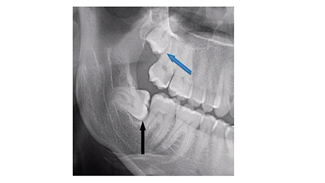

מתי חייבים לעקור שיני בינה?

ד"ר דבורה שוורץ-ארד מאת: ד"ר דבורה שוורץ-ארד 18/06/2018

שיני בינה, כלואות, מהן? מדוע מדובר במצב שמסכן את בריאות הפה והשיניים וכיצד יודעים שחייבים לעקור? מומחית עם כל התשובות לכתבה המלאה